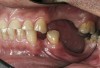

Figure 3  Intraoral occlusal view of mandibular dentition with the existing removable prosthesis presenting excessive signs of wear.

Figure 3

Initial examination revealed a partial edentulous patient with extensive wear of the maxillary anterior teeth and moderate wear in the mandibular teeth (Figure 1, Figure 2, Figure 3, Figure 4, Figure 5, Figure 6 and Figure 7). The patient’s maxillary and mandibular RPDs also showed excessive wear and multiple signs of fractures (Figure 2 and Figure 3). The patient had been wearing a mandibular nightguard for 8 years.